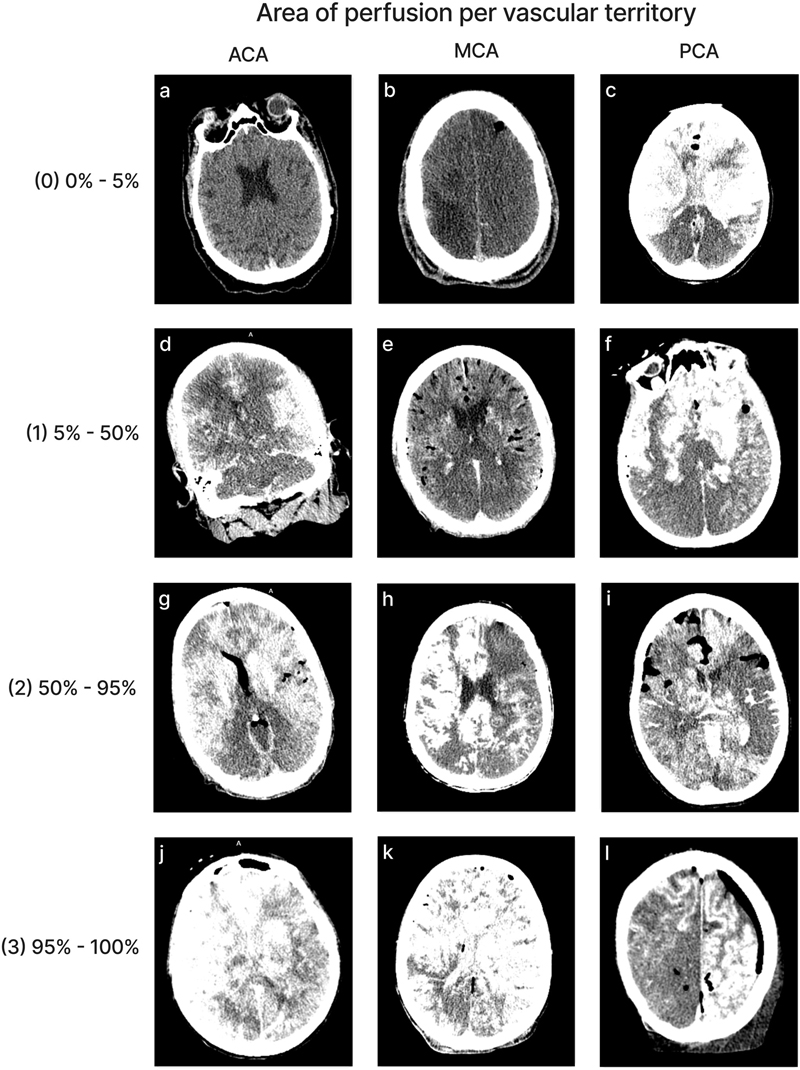

We aimed to perform neuroimaging both before and after perfusion, with the brain remaining inside of the skull. The CT scanner we used was the OmniTom® Elite (Neurologica, Danvers, MA), a 16-slice scanner. Images were viewed with the Osimis Web Viewer. Occasionally, one or both of these CT scans was not performed, for example if the CT scanner was not working at the time. For each of eight major vascular territories – corresponding to the territory supplied by the left and right anterior cerebral artery (ACA), middle cerebral artery (MCA), and posterior cerebral artery (PCA), as well as the cerebellum, we graded the extent of contrast visualized on the post-perfusion CT scans in a given territory on a 0–3 scale, with 0 indicating < 5 % extent of perfusion, 1 indicating 5–50 %, 2 indicating 50–95 %, and 3 indicating > 95 %. In some cases, the grades could not be completed for some of the areas in the brain because the available CT scan contained only part of the brain, not the whole brain. The extent of air bubbles in the CT scan across the brain was also graded on a 0–3 scale, with 0 indicating no apparent air bubbles, 1 minimal, 2 moderate, and 3 substantial. This grading was performed on all of the post-perfusion CT scans available via the collaboration of two graders. For a brain-wide assessment measure, we generated a separate score based on the sum of the grades across all evaluated areas, excluding cases with missing data from any vascular territory.

Quality of perfusion in CT images

Perfusion quality based on CT scans was graded on a semi-quantitative scale, reflecting the estimated percentage of contrast agent present in different brain regions (Figure 4). We also developed a semi-quantitative grading scale to assess the extent of air bubbles observed in some CT scans (Figure 5). For a subset of cases, the images were graded separately by two independent raters, yielding an ICC of 0.536 (95 % CI: 0.293–0.705), indicating fair interrater reliability. Consistent with the observations from gross examination images, the CT scans revealed patchy distribution of contrast in nearly all cases, both across and within vascular territories.

Figure 4.

Representative images of CT scans that demonstrate the grading schema. All images show the grading for both the left and right sides of the respective region, except for image(l), in which only the left side represents the correct grading. Images follow the standard radiological convention, with the right side of the image corresponding to the donor’s left side and vice versa. Donor IDs: 136 (a), 71 (b), 185 (c), 179 (d), 197 (e), 201 (f), 195 (g), 5 (h), 84 (i), 203 (j), 206 (k), 142 (l).

The mean perfusion quality grades based on CT scans across both hemispheres were 1.94 ± 0.09 for the ACA distribution, 1.80 ± 0.09 for the MCA, 1.33 ± 0.09 for the PCA, and 1.32 ± 0.07 for the cerebellum (Figure 6). There was no significant difference between the grades in the ACA and MCA distribution (t-test p-value = 0.27). The grades in the ACA and MCA were each significantly higher than those in the PCA (t-test, p-values = 2.6e-6 and 0.0003, respectively) and the cerebellum (t-test, p-values = 2.3e-7 and 6.8e-5, respectively). Therefore, as with the gross examination data, average perfusion quality graded on CT scans was found to be higher in the regions supplied by the anterior circulation than in those supplied by the posterior circulation.